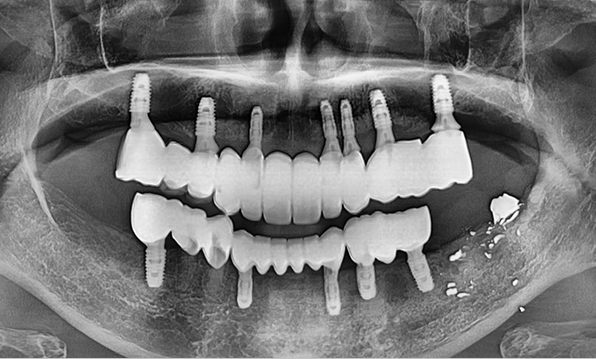

Minimal Placement

Using a method of placing 6–7 implants in the maxilla and 6 in the mandible, this approach restores both posterior and anterior teeth, efficiently rehabilitating the entire oral cavity.

Before After